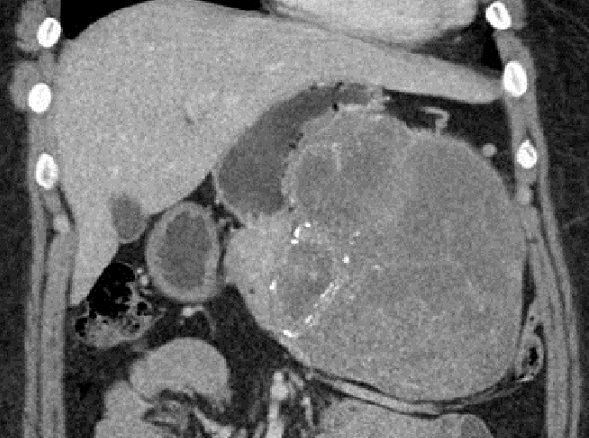

Aspect

lesionnel une grand kyste hydatique l du pancreas a

phase transitional de type II de Gharbi . Sa paroi

et les septal se en voyant tres nette apres

injection de contrast a phase veineuse ( signe de

rehaussement ) . Image radiologique TDM plus C+

phase veineuse , coupe axiale . |

Image radiologique IRM ponderee sur

T2 d'une kyste hydatique active de type I de Gharbi

avec aspect lesionnel d'une formation kystique

arrondie tres hypersignal a bord nette , lisse et

regulier situe au corp du pancreas . Sa contenue est

de collection liquidienne pure , cela se donne une

image de tres hyperintense sur la coupe IRM

ponderee T2 |